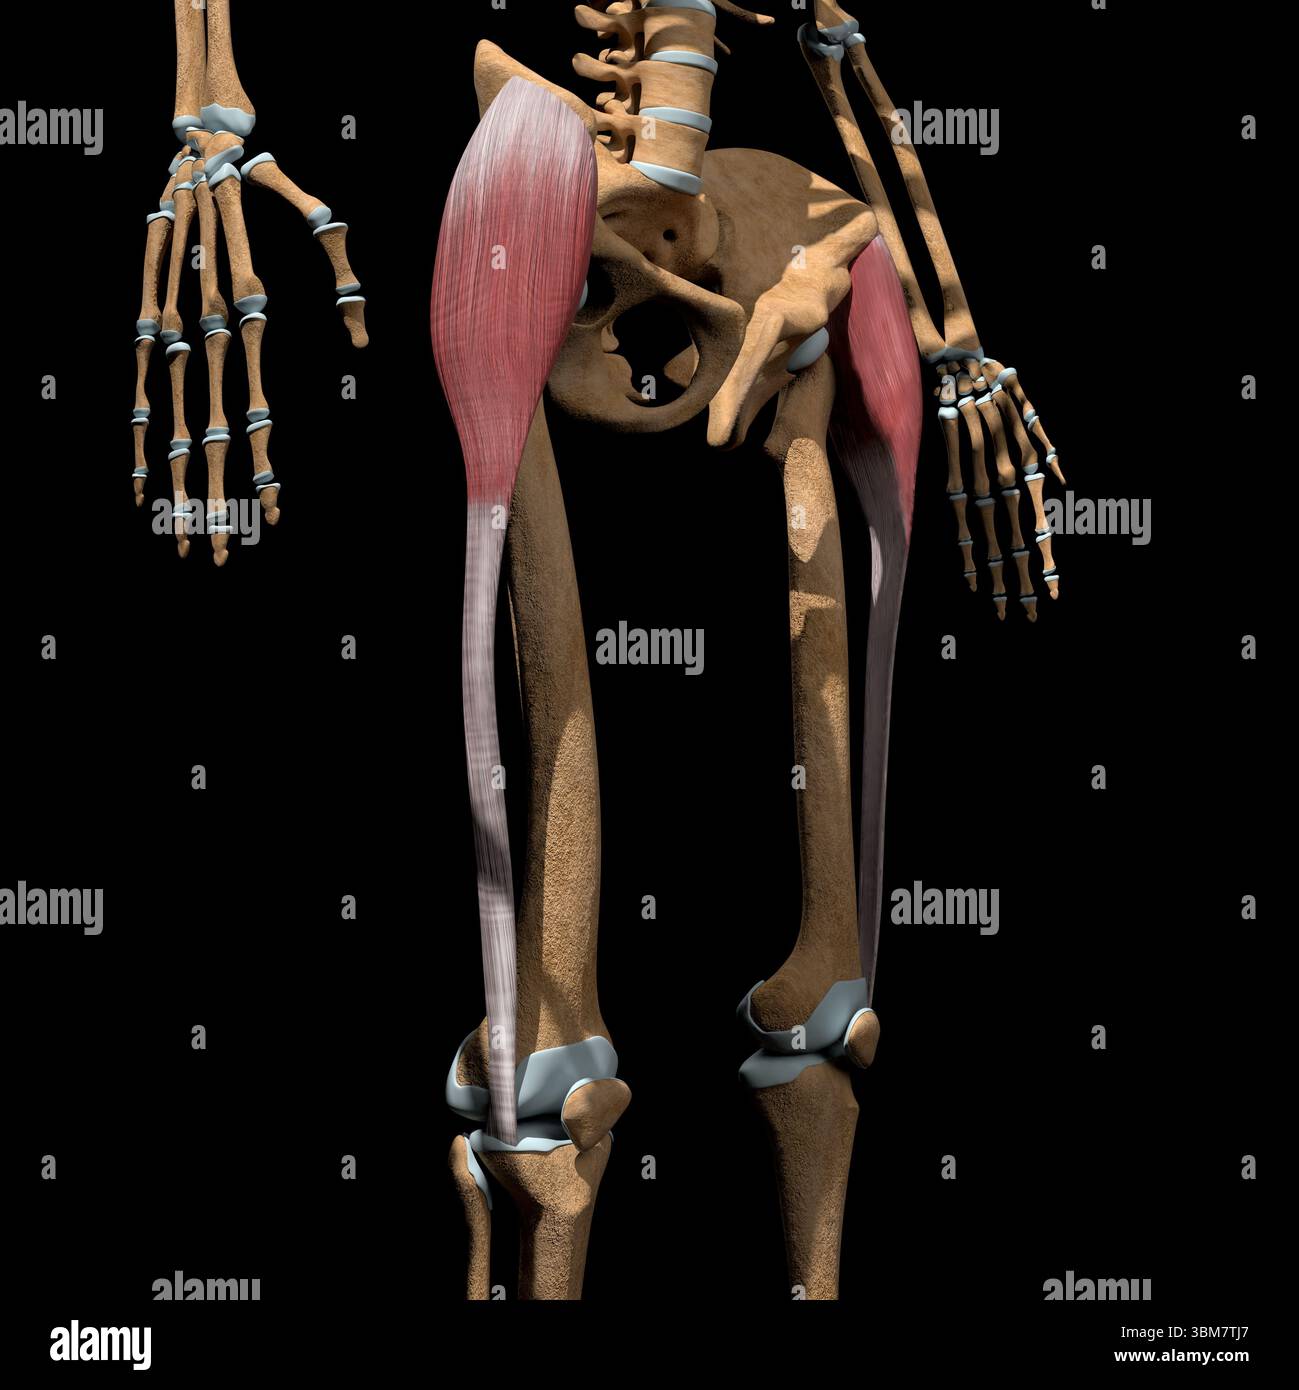

This 3d illustration shows the tensor fasciae latae muscles on skeleton. Stock Photohttps://www.alamy.com/image-license-details/?v=1https://www.alamy.com/this-3d-illustration-shows-the-tensor-fasciae-latae-muscles-on-skeleton-image683670463.html

This 3d illustration shows the tensor fasciae latae muscles on skeleton. Stock Photohttps://www.alamy.com/image-license-details/?v=1https://www.alamy.com/this-3d-illustration-shows-the-tensor-fasciae-latae-muscles-on-skeleton-image683670463.htmlRF3BM7TJ7–This 3d illustration shows the tensor fasciae latae muscles on skeleton.